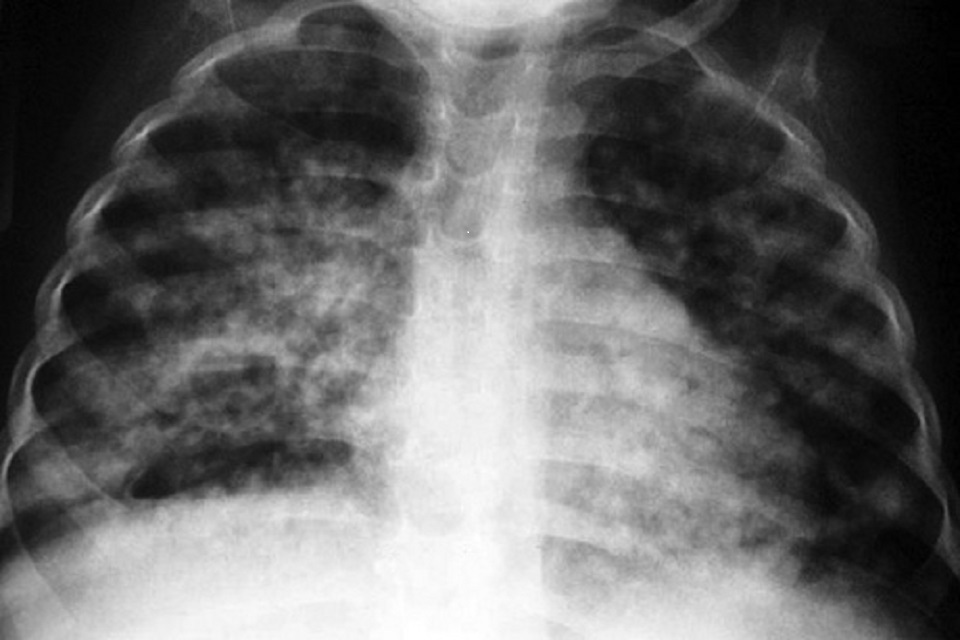

Although England continues to be a low incidence country for tuberculosis (TB), decline in rates has levelled off.

Despite an overall downward trend in the number and rate of TB notifications in England during the last 10 years, the rate of decline has slowed in the last 4 years. Unless immediate action is taken, England will fall short of achieving the World Health Organization (WHO)’s End TB Strategy target of 90% reduction in people with TB from 2015 to 2035.

In 2021, the incidence of TB stood at 7.8 notifications per 100,000 people, compared to 8.4 notifications per 100,000 in 2019. Although this is a decline since before the pandemic, in order to hit the WHO elimination target by 2035, we need to see a reduction in TB rates to 1.05 per 100,000. If we continue at the current rate of decline, we will only hit 5.1 per 100,000 by 2035. Provisional data from 2022 indicates we remain off trajectory.